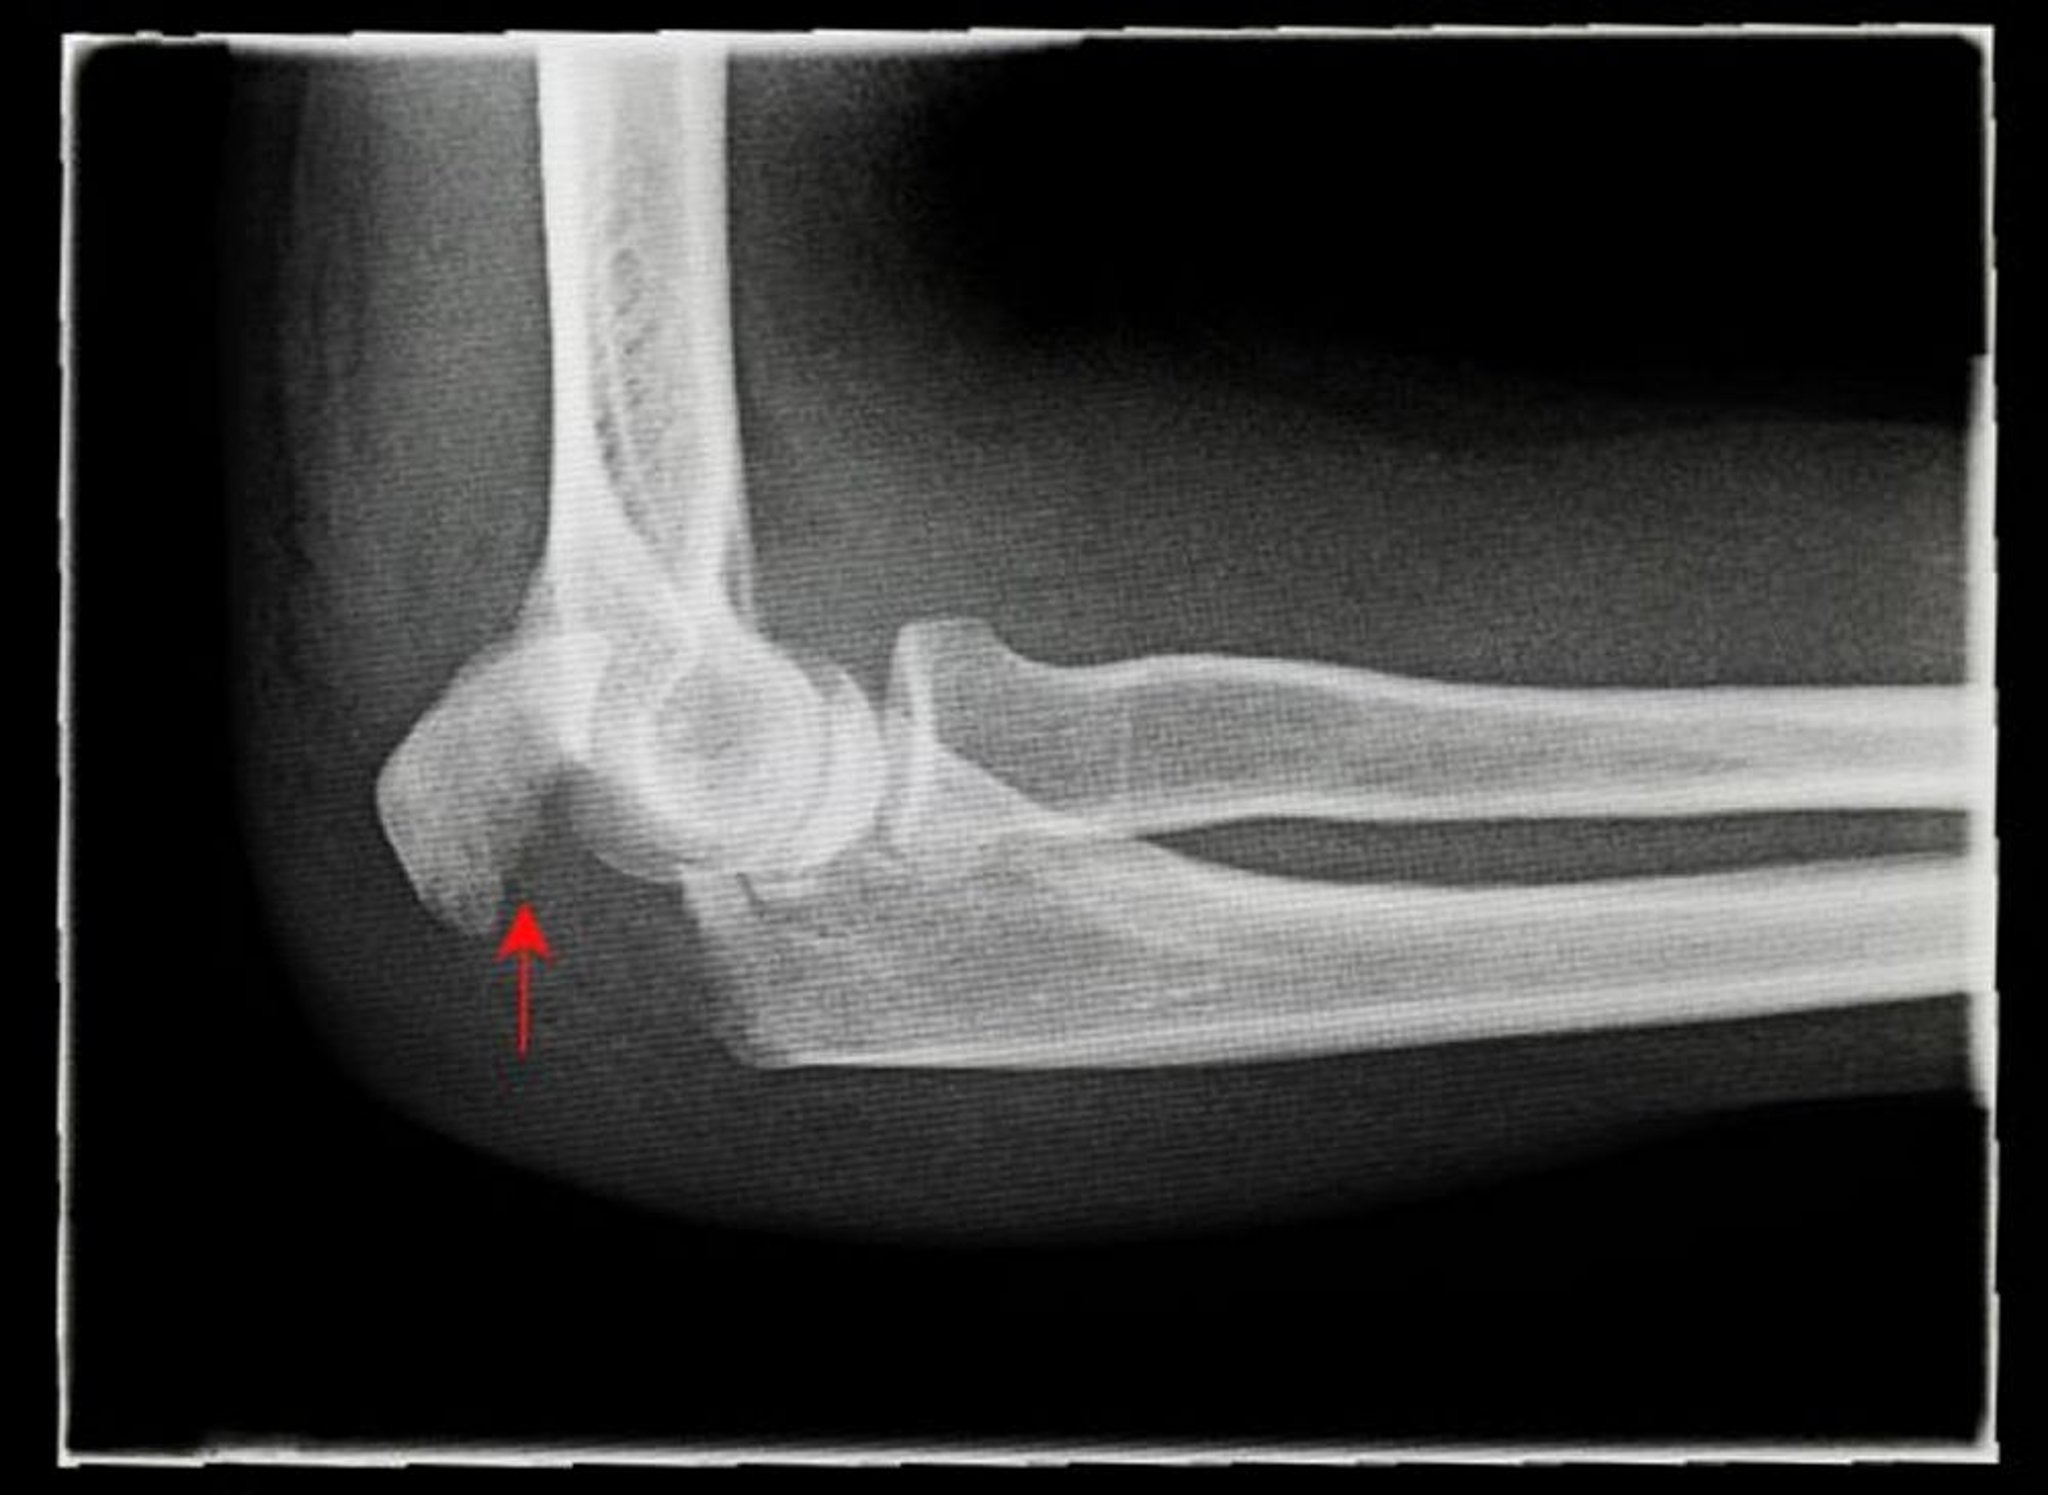

전위 팔꿈치머리 골절

이 x-레이는 전위 팔꿈치머리 골절(화살표)의 측면도를 보여줍니다.